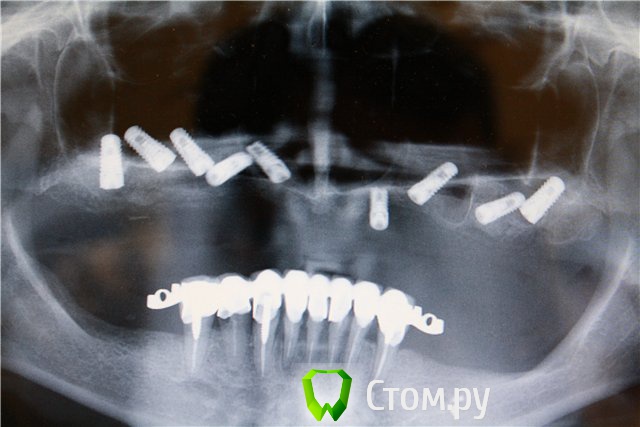

Doc Опубликовано 27 мая, 2014 Поделиться Опубликовано 27 мая, 2014 Исходя из логики Александра в этом посте хочется выступить против еще одной системы имплантатов. Раз на примере одного клинического случая с одним имплантатом можно делать выводы о качестве системы, то мало кто откажет мне в том, что на примере девяти имплантатов я могу делать железобетонные заключения о качестве системы! Неправда ли? Просто отвратительная, ужасная, мерзкая система имплантатов. Какая бешенная резобция (пардон, ремоделировка!), какая жуткая первичная стабильность, да и ставятся они по оси как-то криво! Фу!!! Просто ФУ-ФУ-ФУ!!!!!!!!! )) 1 Ссылка на комментарий

Bobby Опубликовано 27 мая, 2014 Поделиться Опубликовано 27 мая, 2014 Исходя из логики Александра в этом посте хочется выступить против еще одной системы имплантатов. Раз на примере одного клинического случая с одним имплантатом можно делать выводы о качестве системы, то мало кто откажет мне в том, что на примере девяти имплантатов я могу делать железобетонные заключения о качестве системы! Неправда ли? 7cc734339609.jpg Просто отвратительная, ужасная, мерзкая система имплантатов. Какая бешенная резобция (пардон, ремоделировка!), какая жуткая первичная стабильность, да и ставятся они по оси как-то криво! Фу!!! Просто ФУ-ФУ-ФУ!!!!!!!!! ))))))))) Ссылка на комментарий